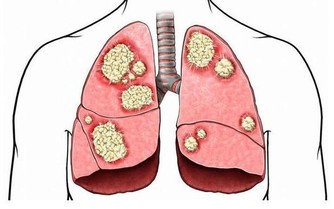

因為肝臟是唯一沒有痛感神經的器官,所以無論它累成怎麼樣,它也從不呻吟叫苦,也不會喊痛,這也是人們經常忽略它健康狀況的根本原因。這就是為什麼肝癌一發現,就是晚期的原因。

肝臟其實是一個非常重要的髒器,它掌管著糖、脂肪、蛋白質的解毒、代謝,人體大部分的新陳代謝和有毒物質的轉化,因此,它也是最易污染的部門。